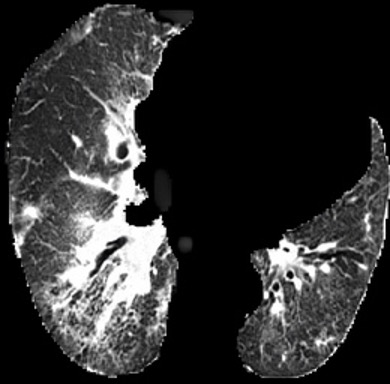

In the field of medical imaging, particularly in tasks related to early disease detection and prognosis, understanding the reasoning behind AI model predictions is imperative for assessing their reliability. Conventional explanation methods encounter challenges in identifying decisive features in medical image classifications, especially when discriminative features are subtle or not immediately evident. To address this limitation, we propose an agent model capable of generating counterfactual images that prompt different decisions when plugged into a black box model. By employing this agent model, we can uncover influential image patterns that impact the black model's final predictions. Through our methodology, we efficiently identify features that influence decisions of the deep black box. We validated our approach in the rigorous domain of medical prognosis tasks, showcasing its efficacy and potential to enhance the reliability of deep learning models in medical image classification compared to existing interpretation methods. The code will be publicly available at https://github.com/ayanglab/DiffExplainer.